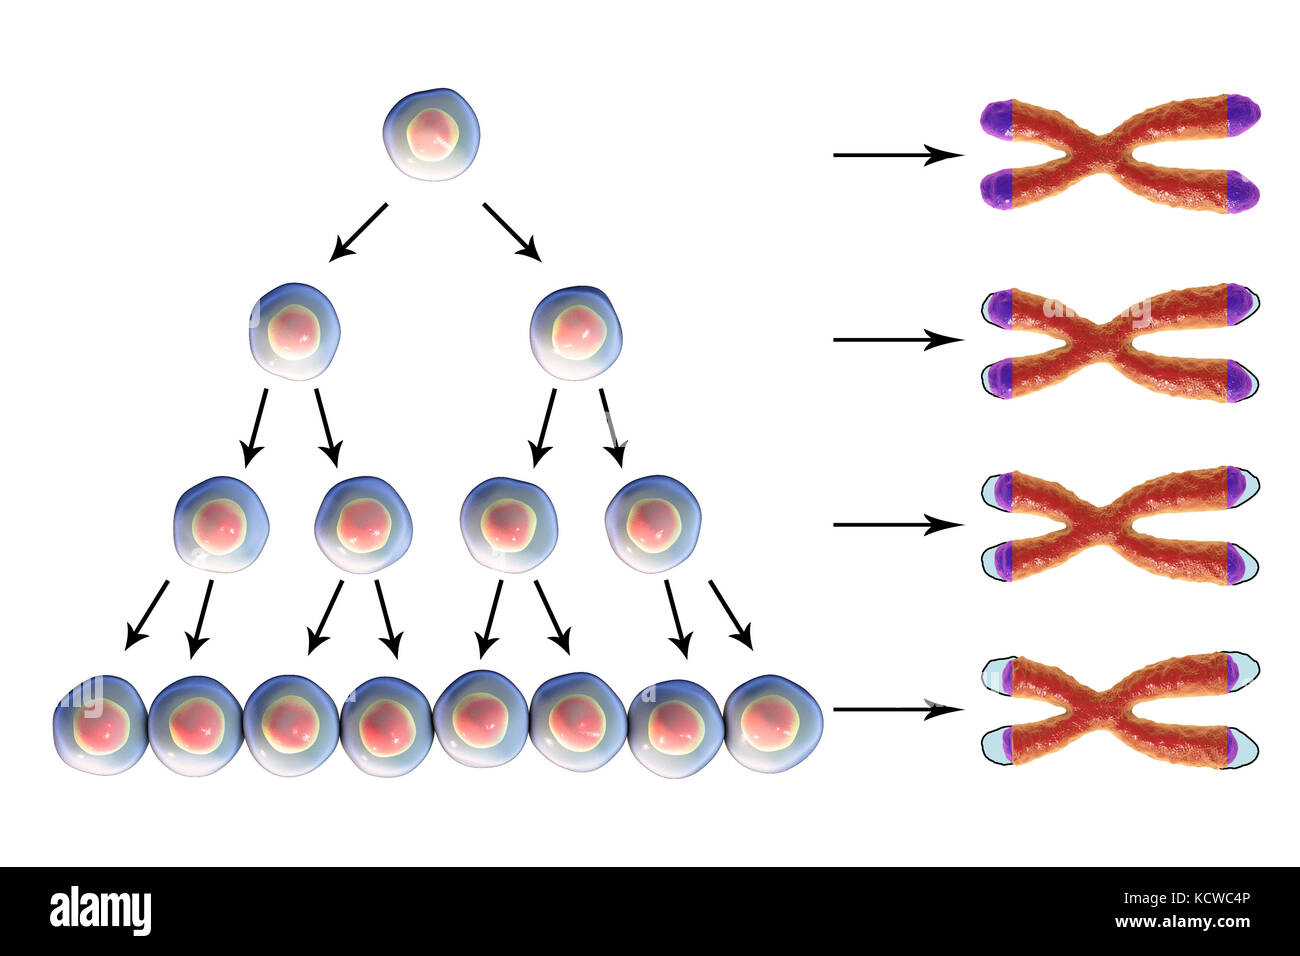

RFKCWC4N–Le raccourcissement des télomères avec chaque cycle de division cellulaire, l'illustration conceptuelle. Les télomères, les bouchons sur les chromosomes, raccourcir avec l'âge et au cours de différents processus pathologiques.

RFKCWC4P–Le raccourcissement des télomères avec chaque cycle de division cellulaire, l'illustration conceptuelle. Les télomères, les bouchons sur les chromosomes, raccourcir avec l'âge et au cours de différents processus pathologiques.